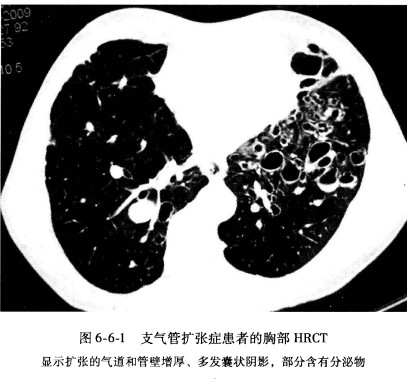

高分辨率CT[编辑 | 编辑源代码]

胸部HRCT诊断支气管扩张症的敏感性和特异性均达到了90%,是支气管扩张症的首选检查手段。普通胸部CT扫描也可诊断支气管扩张,但敏感性仅有66%。支气管扩张在HRCT上的特征性表现包括:支气管扩张,支气管管壁增厚,支气管由中心向外周逐渐变细的特点消失以及扩张气管内气液平的存在。当支气管内径大于相伴行走的支气管动脉时,可以考虑支气管扩张的诊断。